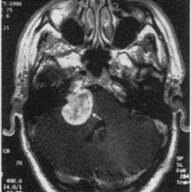

МРТ головного мозга (Т2-взвешенное изображение): глиома больших размеров в правом полушарии, сдавливающая и смещающая его желудочковую систему

Глиобластома - достаточно злокачественная глиальная опухоль. Встречается у взрослых, чаще у мужчин в височной доле головного мозга. Имеет большое количество сосудов, артериовенозных шунтов, быстрое ин-сультоподобное течение, возможны кровоизлияния в опухоль. Продолжи­тельность жизни в таком случае не превышает 9-12 мес.